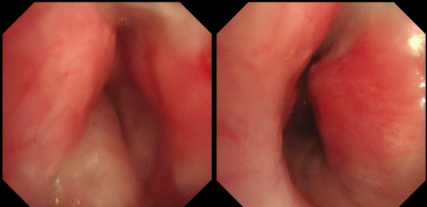

日前,患者趙先生(化名)因進(jìn)行性呼吸困難來到河南省胸科醫(yī)院尋求治療,經(jīng)檢查確診為支氣管結(jié)核導(dǎo)致氣管中下段重度瘢痕性狹窄,最窄處直徑僅約3mm,且局部軟骨環(huán)破壞、塌陷,這意味著支撐氣道的結(jié)構(gòu)遭到損毀,通氣功能嚴(yán)重受損,且因狹窄部位靠近隆突,治療操作風(fēng)險(xiǎn)極高,稍有不慎就可能導(dǎo)致大出血、氣道完全閉塞等致命并發(fā)癥。

面對(duì)這一復(fù)雜情況,呼吸內(nèi)鏡中心主任王振靜組織結(jié)核內(nèi)科、麻醉科、醫(yī)學(xué)影像科等多學(xué)科會(huì)診。經(jīng)全面評(píng)估,團(tuán)隊(duì)制定了詳細(xì)的手術(shù)方案:在全麻下,先行球囊擴(kuò)張狹窄段,再經(jīng)硬質(zhì)支氣管鏡置入個(gè)體化制作的Y型硅酮支架,以支撐氣道結(jié)構(gòu)、恢復(fù)通暢。

在硬質(zhì)支氣管鏡引導(dǎo)下,手術(shù)團(tuán)隊(duì)首先對(duì)狹窄部位進(jìn)行球囊擴(kuò)張。隨后,將術(shù)前根據(jù)患者三維CT數(shù)據(jù)定制的Y型硅酮支架精準(zhǔn)覆蓋于氣管狹窄段。該支架確保與患者自身的氣道解剖結(jié)構(gòu)完美貼合,實(shí)現(xiàn)最佳支撐效果,并最大限度減少粘膜刺激增生等特點(diǎn)。支架展開后穩(wěn)定支撐于隆突及雙側(cè)主支氣管,氣道狹窄立即得到解除。